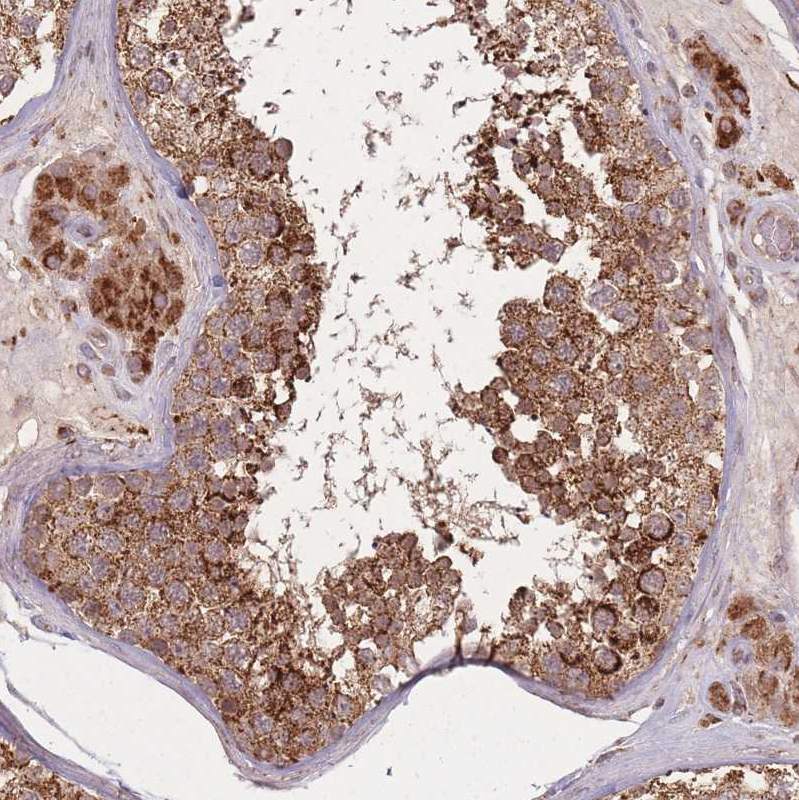

Immunohistochemical staining of human Testis shows strong granular cytoplasmic positivity in cells in seminiferous ducts and Leydig cells.